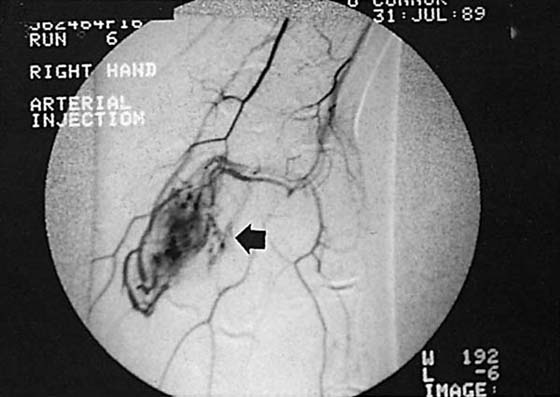

Arteriography

Arteriography is the most specific means of evaluating vascular anatomy and pathology; it is used to evaluate aneurysms, arteriovenous malformations, tumors of vascular origin, traumatic vessel injuries, and solid tumor vascularity (Fig. 13-15).8,15 The examination is performed by threading a catheter into the brachial artery using a femoral approach, injecting contrast material, and then taking multiple radiographs. The procedure is often painful, even with the use of new nonionic contrast material. Complications include bleeding hematoma, pseudoaneurysm formation, dissection, and thrombosis. The contrast medium may cause arterial spasm, although this can be controlled with the use of vasodilators. Anaphylaxis is another potential complication when iodinated contrast material is used, but severe episodes are rare, occurring in only 1 of 40,000 cases.

images

Figure 13-15 Contrast arteriogram of the wrist showing a hemangioma (arrow) in the ulnar aspect of the palm.